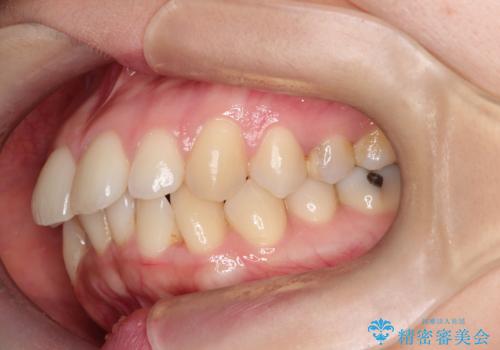

- 治療計画

- 「歯のデコボコと前歯が出ているせいで口が閉じにくい」を主訴に来院された患者様です。

上下左右の4番(第一小臼歯)を抜歯をし審美ワイヤー装置で治療を行いました。

抜歯矯正により歯列のデコボコ(叢生)が改善し、前歯の突出も解消されたことで口元が下がり、すっきりとした印象となりました。

患者様にも大変ご満足いただけました。